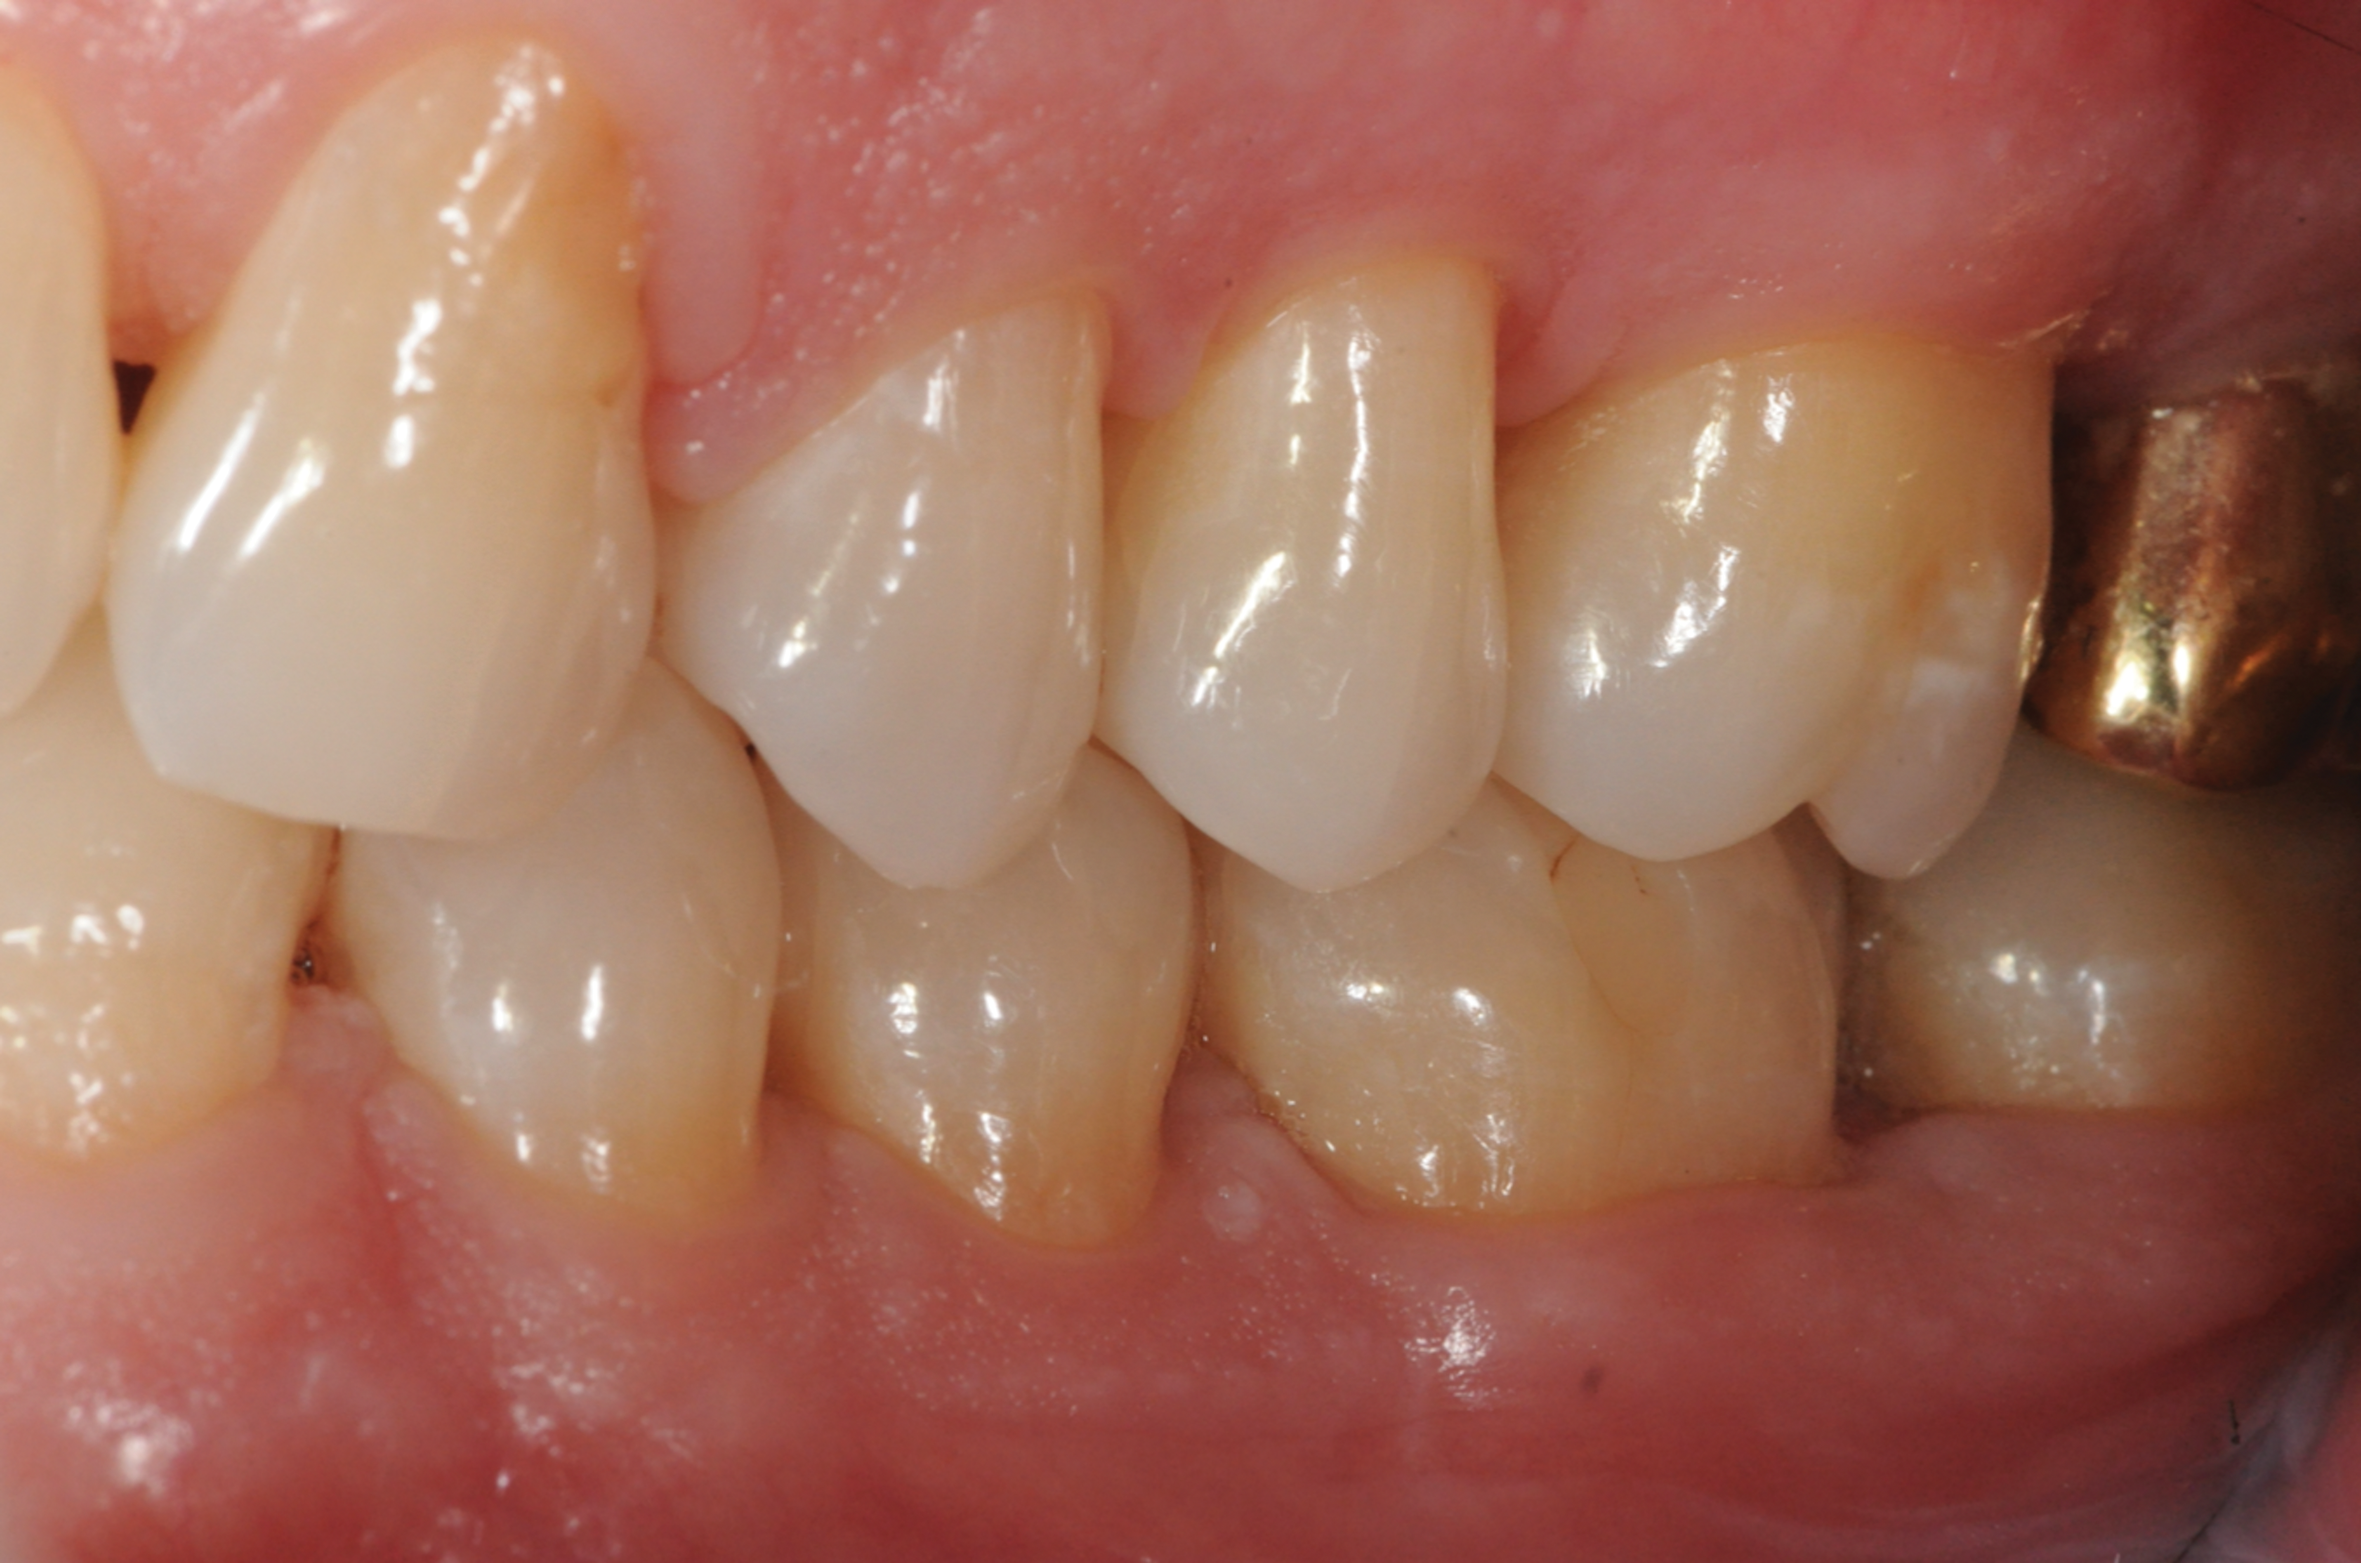

Fig 13. Stability of the soft tissues at 1-year follow-up.

Figure 13

Fig 14. Periapical radiograph revealing healed bone at 1-year follow-up.

Figure 14

In the present case, the patient's postoperative protocol included the administration of analgesics and mouthrinse. Plaque control and polishing were performed every 2 to 3 weeks for the first 3 months. The patient was then placed on a 3-month recall system. At the 1-year follow-up, stability of the soft and hard tissues could be observed (Figure 13 and Figure 14). Following the seven-key checklist, this clinical case demonstrated that correct case selection, with consideration given to patient-, tooth-, defect-, and operator-related factors, combined with the use of an evidence-based surgical protocol, led to predictable outcomes.